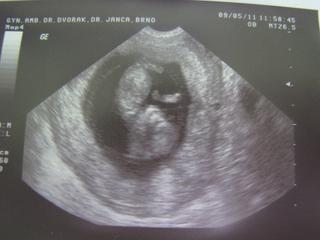

Ahojky, tak poradna v pořádku, vše vypadá, že je tak ,jak má být a jsem dneska 11+2, čili 12 týden a mimčo vypadá, že je o týden starší než dle MS, podle které bych měla být 10+2, takže se rodit bude koncem listopadu,ale uvidím příští týden na NT+ jak mi dle UTZ stanoví TP.Mimčo sebou nádherně mlelo, kopalo a mávalo ručičkama, se mi chtělo i brečet 😀 , úplný opak Nathy, která pořád jen spala a na utz ji museli budit aby se vůbec pohla a to taky ne vždy se podařilo,t akže toto bude asi pěkný kvítko 😀